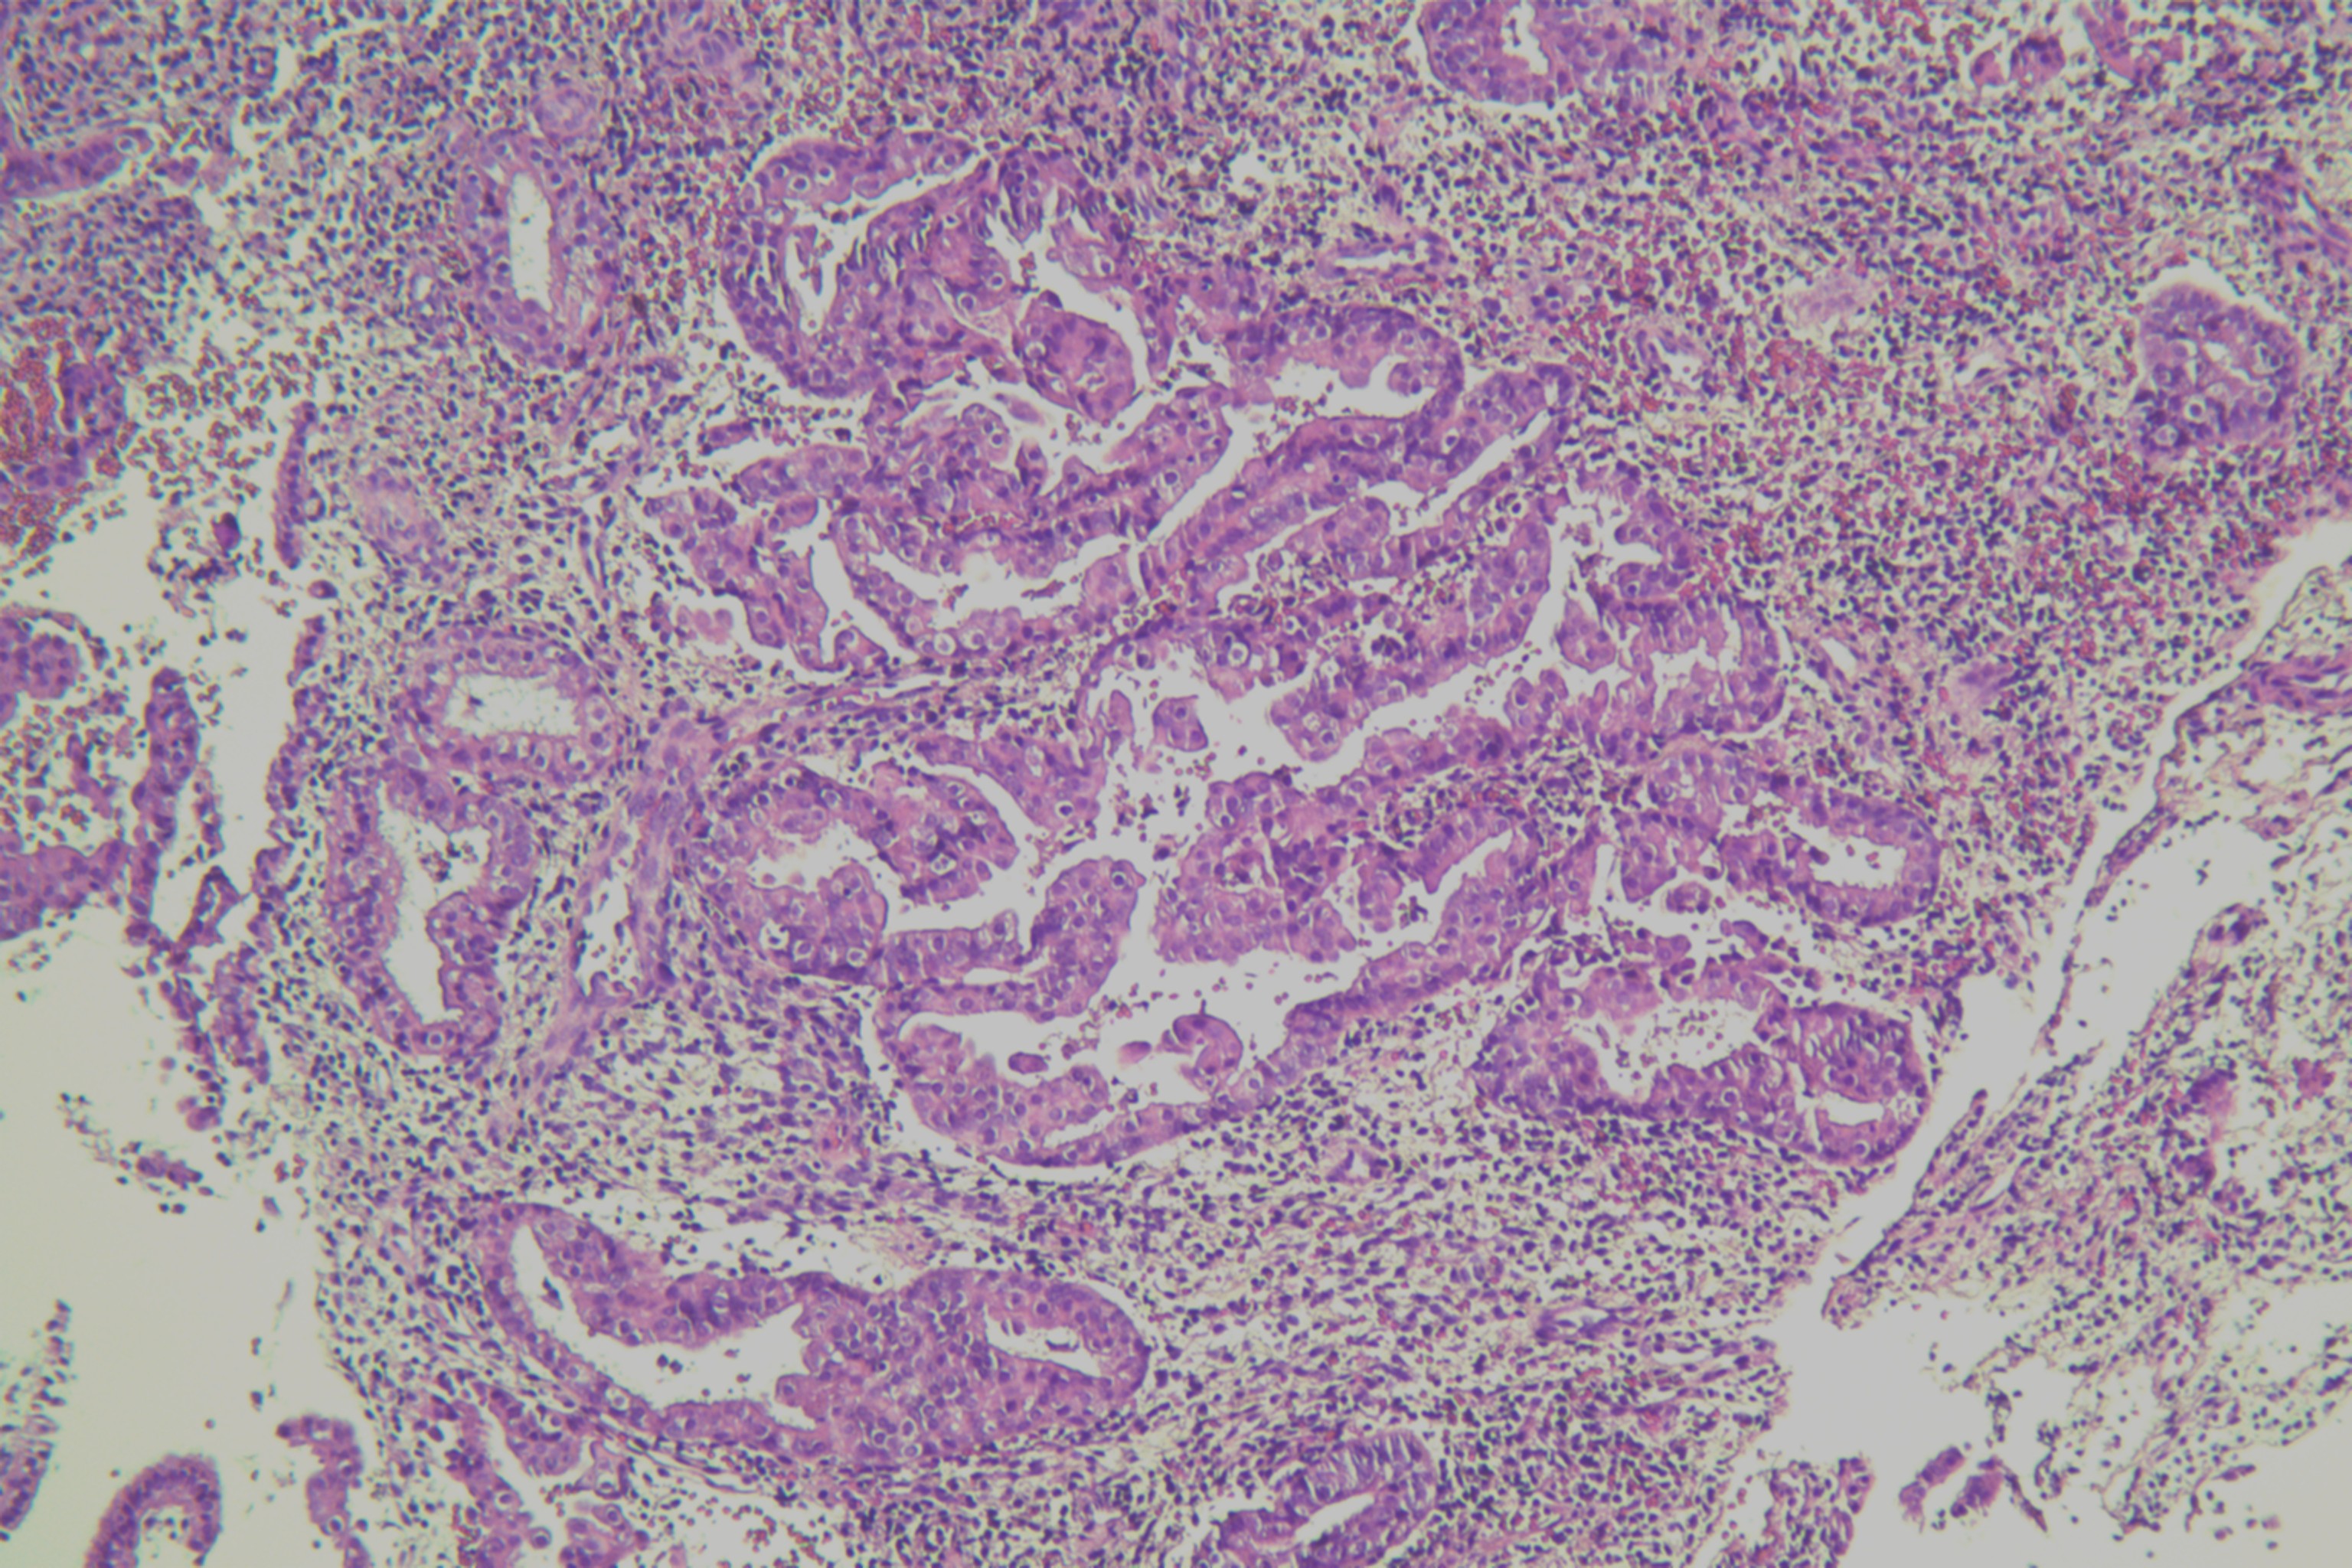

子宫内膜有无非典型性?

月经紊乱1年余,子宫增厚11月

宫腔刮出物

2.8*2.3*0.5cm灰红碎组织一堆。

嗜酸性乳头状化生。

未见非典型增生考虑为子宫内膜单纯性增生部分区域腺体呈复杂性增生(图6)伴部分腺体呈嗜酸性乳头状化生

局灶非典型性增生伴嗜酸性乳头状化生